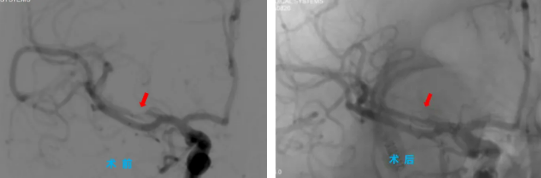

手術(shù)當(dāng)天,院長助理、神經(jīng)內(nèi)科主任程偉與神經(jīng)內(nèi)科三病區(qū)副主任彭偉聯(lián)手為患者主刀,通過高難度的微創(chuàng)介入治療,成功為患者大腦中堵塞的血管進行了球囊擴張并置入支架,打通了“生命通道”。術(shù)后,患者手腳能活動了,說話也清楚了,恢復(fù)得一天比一天好,一周后,患者康復(fù)出院。